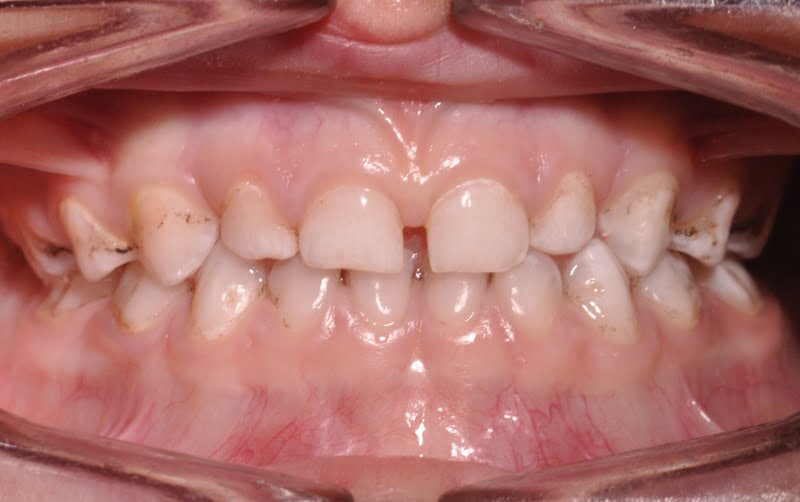

T.G., paciente do sexo masculino, com quatro anos de idade, dentição temporária completa, sem antecedentes médicos relevantes e com história prévia de falta de colaboração nas consultas de medicina dentária.

Foi realizado um exame clínico e radiológico inicial (fig. 1 a 3), tendo sido diagnosticada, entre outras lesões de cárie, uma lesão de cárie profunda com atingimento pulpar no segundo molar temporário inferior direito (fig. 3). Foi proposta a realização de uma pulpotomia com agregado trióxido mineral (MTA) e a colocação de uma coroa pré-formada. As várias possibilidades restauradoras foram apresentadas e discutidas com os pais, que decidiram optar pela colocação de uma coroa pré-formada de zircónia, por motivos estéticos.